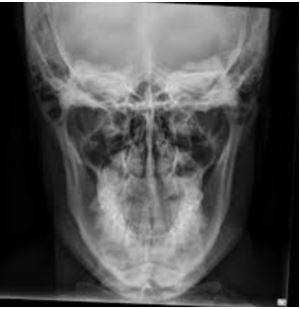

Рентген нижней челюсти

Чтобы получить общую информацию о состоянии нижней челюсти, выполняется рентген-снимок в прямой проекции. Он позволяет проводить первичную диагностику воспалительных, онкологических и травматических заболеваний. Пациента укладывают следующим образом: лежа на животе, лицом книзу, опираясь кончиком носа и лбом о кассету. Датчик рентгеновского аппарата устанавливается у затылочного бугра.

Снимок нижней челюсти в боковой проекции выполняют для оценки состояния тела, ветви и зубов нужной стороны. Пациент ложится на бок, щекой на кассету, расположенную под небольшим наклоном.

Для диагностики заболеваний нижней челюсти выполняются снимки и в аксиальной проекции. Пациент занимает позу лёжа на животе, максимально вытягивая голову подбородком вперед. К кассете при этом он прижимается передней поверхностью шеи и нижней челюстью.

Рентген верхней челюсти

Для оценки состояния костной ткани верхней челюсти и подбородочной области нижней челюсти выполняется носоподбородочная укладка. Для этого пациент ложится на живот, лицом книзу, опираясь кончиком носа и подбородком о кассету. Датчик устанавливается перпендикулярно кассете, делается 2 снимка - с открытым и закрытым ртом.

Панорамный снимок челюсти

Панорамный рентген-снимок, или ортопантомограмма, отображает полностью верхнюю и нижнюю челюсти в прямой проекции. На таком снимке можно увидеть практически все анатомические особенности зубочелюстной системы пациента, всевозможные новообразования, дефекты, переломы корней зубов и так далее. Ортопантомограмма позволяет выявить следующие патологии:

Расшифровка результатов

Расшифровывает снимки рентгена челюсти взрослого человека обычно врач-рентгенолог. Также к этой работе могут привлекаться и другие специалисты: стоматолог, лицевой хирург, отоларинголог. Конкретные патологии верхней и нижней челюстей имеют определённые рентгенологические особенности: